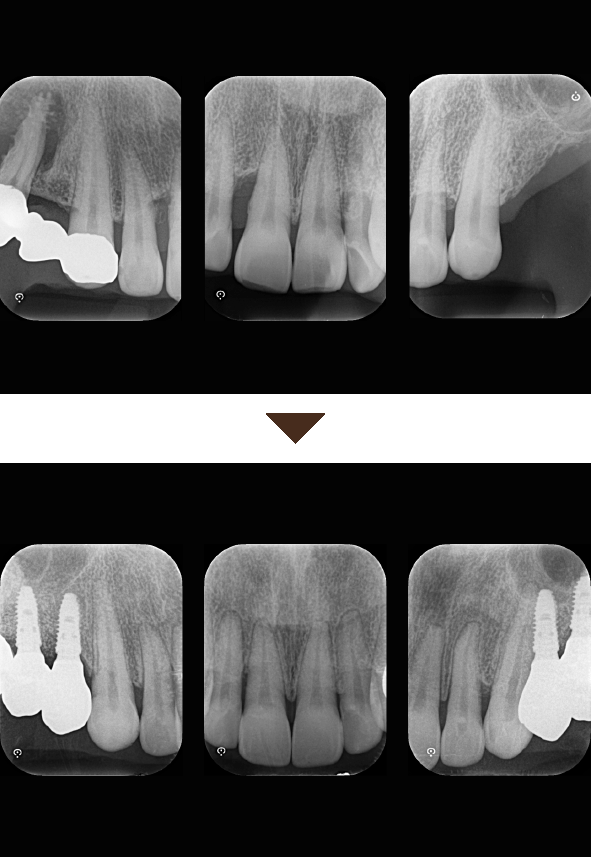

歯周組織再生療法は施術の難易度が高く、ほとんどの歯科では扱っていない内容です。

専門医資格を持つ医師が歯周組織再生治療を手がけるので、安心して治療を受けていただけます。